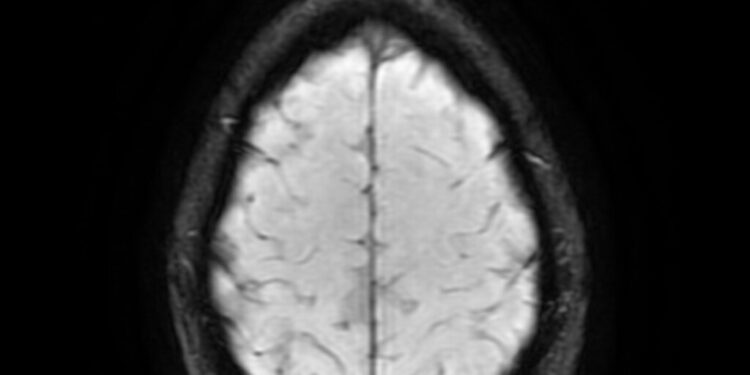

A new study from Sweden suggests that improving cardiorespiratory fitness (CRF) may help reduce the risk of dementia, even for people with a genetic predisposition to the condition. CRF measures how well the heart and lungs deliver oxygen to muscles during physical activity, and it tends to decline with age, starting in the 20s and continuing to decrease significantly as people reach their 70s. Low CRF is linked to increased risks of heart disease, strokes, and early death.

Overall, the researchers call for further studies to explore the relationship between CRF and brain health, especially its potential in mitigating the impact of genetic risk factors for dementia. Enhancing CRF may offer a non-invasive way to help prevent cognitive decline and improve overall brain function in aging individuals.